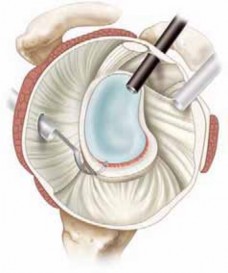

Following the diagnostic sweep, two anterior working portals are established using an outside-in spinal needle localization technique. The anterosuperior portal is typically placed just anterior to the acromioclavicular joint, entering the joint through the rotator interval superior to the biceps tendon; this serves primarily for fluid management and suture retrieval. The critical anteroinferior working portal is placed just superior to the upper border of the subscapularis tendon, ensuring an optimal trajectory (approximately 45 degrees to the glenoid face) for anchor insertion along the anteroinferior glenoid rim. A clear cannula (typically 5.5 mm or 8.25 mm) is introduced to facilitate smooth instrument passage and suture management.

The foundation of a successful arthroscopic stabilization is the meticulous mobilization of the capsulolabral complex. In chronic cases, the torn labrum and IGHL frequently heal in a medially displaced position along the anterior glenoid neck (the ALPSA lesion). Using a combination of arthroscopic elevators, rasps, and electrocautery, the surgeon must aggressively liberate this tissue from the scapular neck. The release must extend inferiorly to the 6 o'clock position to adequately mobilize the inferior capsule. Once the tissue is freed and can be easily reduced to the articular margin, the anterior glenoid neck is lightly decorticated using a motorized burr or rasp. This critical step removes fibrous tissue and exposes bleeding cancellous bone, creating an optimal biological environment for robust soft-tissue healing.